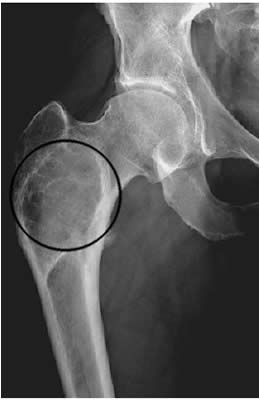

- Radiografia (RX): è quasi sempre il primo esame eseguito. L’aspetto radiografico tipico delle lesioni è quello a “vetro smerigliato” (ground glass), dovuto alla sovrapposizione di numerose trabecole ossee immature. I margini della lesione sono spesso sfumati e si fondono con l’osso sano circostante. L’aspetto può tuttavia variare, presentandosi anche come radiotrasparente (simil-cistico), sclerotico o misto.

In generale, le sedi scheletriche più comunemente colpite dalla displasia fibrosa includono: ossa del cranio e facciali, femore, tibia, coste, omero e bacino. Nelle forme monostotiche, le ossa mascellari sono i siti maggiormente coinvolti.

| Monostotica | È la forma più diffusa e interessa un solo osso. Le sedi più frequenti sono il femore, la tibia, le coste e le ossa mascellari. |